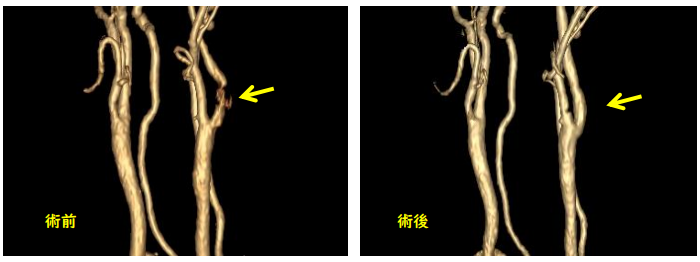

① 頚動脈内膜剥離術(動脈血栓内膜摘出術(内頚動脈))

アテローム硬化を来した頚動脈を直接露出し、血管を切開してプラークを取り除きます。

前述したプラークは総頚動脈が内頚動脈と外頚動脈に分岐する部位で生じ、これら血管を露出するため、病側の前頚部の皮膚を切開して手術を行います。

血管を露出した後に、血管壁を切開し、プラークを摘出します。血管壁の凹凸を修復した後に、血管壁を縫合します。

手術前日に入院し、入院翌日に手術を行います。手術当日はナースステーション隣にある重症患者病室で慎重に経過を観察します。翌日朝から歩行、食事を開始し、入院時に入室した病室に戻ります。術後4日目に頭部MRIを行い、脳梗塞など頭蓋内合併症がないか確認し、術後5日目に頚部MRAを行い、手術した頚動脈が広がっているかどうか確認します。問題がなければ、術後1週間後に退院します。入院期間は9日間です。